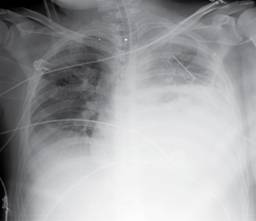

Paciente de sexo masculino de 31 años, referido de centro hospitalario de primer nivel por cuadro de dificultad respiratoria súbita secundaria a hemotórax izquierdo, sin antecedente previo de trauma, el cual fue manejado con sonda pleural con gasto de 1,500 cc al momento de la colocación y enviado a centro hospitalario de tercer nivel para continuar manejo. En la radiografía de tórax inicial se observa una imagen sugestiva de fondo gástrico en el interior de la cavidad torácica izquierda (Figura 1) y debido a que sus signos vitales eran normales, se decidió hacer TC toracoabdominal con doble contraste, en el que se confirma sospecha de hernia diafragmática izquierda, la cual contenía en su interior estómago y grasa mesentérica (Figuras 2 y 3). Se realizó abordaje abdominal línea media, se detectó defecto diafragmático de 3 cm de diámetro, posterolateral izquierdo con contenido no reductible, por lo que fue necesaria la ampliación del defecto; encontrando epiplón y estómago en su interior, este último con paredes isquémicas, zonas necróticas y una perforación de 4 cm de diámetro a nivel de la curvatura mayor (Figura 4), razón por la que se realizó gastrectomía total con anastomosis esófago-yeyunal y reconstrucción en Y de Roux. En el postoperatorio fue trasladado a la unidad de terapia intermedia con apoyo ventilatorio por un periodo de cinco días, además se empleó nutrición parenteral total durante siete días. El quinto día fue valorado por neumología por hallazgos radiográficos de inadecuada expansión pulmonar posterior al evento quirúrgico (Figura 5), refiriéndose la presencia de hipoplasia pulmonar con derrame pleural compensatorio, confirmando la sospecha diagnóstica de hernia de Bochdalek. Fue egresado asintomático 17 días posteriores al procedimiento. El seguimiento actual es de dos años, actualmente se encuentra asintomático, las radiografías de tórax de control sin alteraciones (Figuras 6A y 6B) así como función respiratoria normal.

Figura 1: Radiografía PA de tórax que muestra radioopacidad en hemitórax izquierdo, inseparable de estructuras mediastinales asociada a imagen radiolúcida de aspecto redondeado, la cual condiciona desplazamiento de tráquea hacia la derecha (punta de flecha). Nótese la ausencia de burbuja gástrica en topografía habitual, se aprecia imagen sugestiva de fondo gástrico en hemitórax izquierdo (1), presencia de sonda pleural que penetra por sexto espacio intercostal izquierdo con dirección apical (flecha).